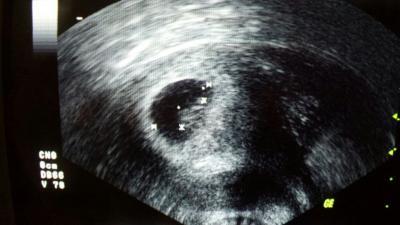

Hallo zusammen, Heute hatte ich den zweiten Termin beim FA. Hatte den ersten ja bei 5+5 und da sah man nur eine Fruchthöhle und den Dottersack. Daher sollte ich zwei Wochen später noch mal vorbeikommen. Und das war also heute bei 7+5. Beim US sah man dann das Baby inkl. Herzschlag. Musste mir die Tränen vor Freude verkneifen. Nur leider war der Drucker für die US-Bilder gerade kaputt gegangen, als die Ärztin drucken wollte. Mein kann hat aber dann ein Bild vom Bildschirm gemacht. Und so kann ich euch unser Würmchen doch zeigen. Habe meinen Mutterpass heute auch wieder bekommen. Der nächste Termin ist am 2.2. Hab noch eine Frage. Empfohlen wurde mir vom FA "Centrum Materna plus DHA" zu nehmen. Habe auch ein paar Probepackungen bekommen. Jetzt habe ich im Internet geschaut und habe die Vermutung, dass diese momentan überall nicht lieferbar sind. Weiß jemand von euch mehr?

Bild zu 2. FA-Termin - Forum für August - Mamis